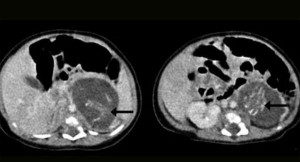

Un bebé de tan sólo tres semanas ha sido operado después de que los médicos descubriesen que estaba ’embarazado’ de tres meses. Este extraño caso, conocido como ‘fetus in fetu’, ha ocurrido en Hong Kong y tan sólo sucede en 1 de cada 500.000 nacimientos en el mundo.

Según explica el diario The Mirror los médicos han tenido que operar al bebé de urgencia para extraerle los dos fetos que tenía en su interior -de ocho y diez semanas de gestación- puesto que para el bebé sería prácticamente imposible llevar a cabo la gestación. Al parecer, los pequeños ya tenían formadas las piernas, los brazos, las costillas, la columna y los intestinos y poseían cordón umbilical.

El especialista chino en ginecología y obstetricia, Dr Yu Kai-man, ha explicado el caso para The Mirror: “Como es imposible para la niña concebir el embarazo por su cuenta, la fertilización de los gemelos pertenece a los padres. Simplemente ‘se fue’ por el lado incorrecto”.